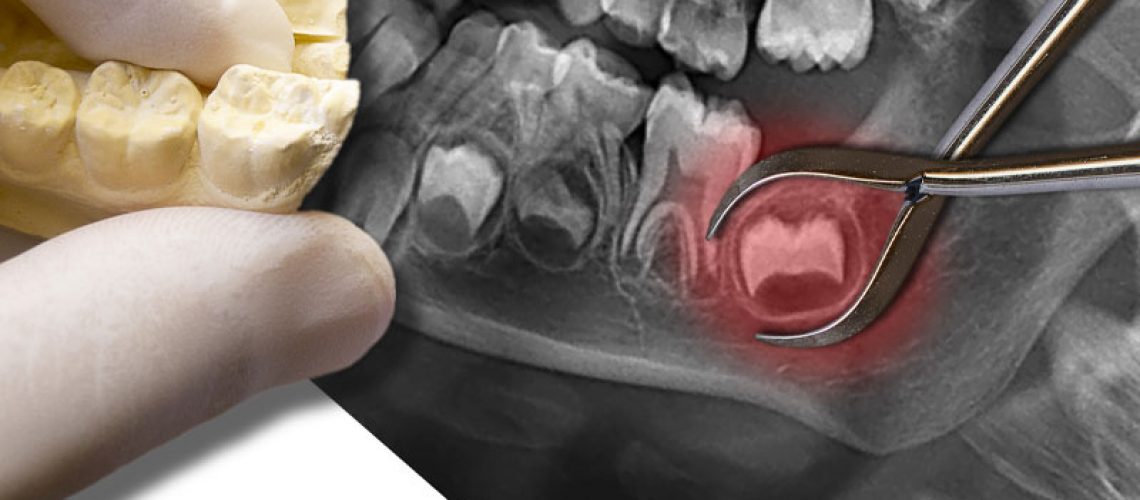

Impacted Wisdom Tooth XRay

People should go to a quality oral surgeon for their wisdom tooth removals. Before their wisdom teeth are even extracted, the oral surgeon will take x-rays of the patients mouth to understand the complexities of their smile and how to best remove their wisdom teeth. From there, the oral surgeon can work on getting the patient ready for their wisdom tooth removal.